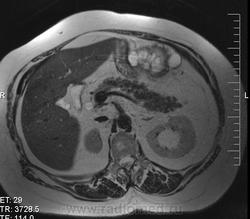

очень характерная картина для метастаза рака яичника, к сожалению.

Не могу достоверно определить локализацию метастаза брюшной полости, вероятно в лимф. узел с инвазией оободочной кишки. Рецидив С-r левого яичника думаю, что с инфильтацией левой стенки прямой кишки и культи влагалища, вторичная лимфаденопатия л/у малого таза. каликопиелоуретероэктазия (инвазия нижних отделов левого мочеточника?) Холедох широковат, но желтухи по внешнему виду нет.

Прорастание левого мочеточника рецидивной опухолью есть 100%, метастаз в большой сальник характерен для рака яичников, как и сигнальные характеристики его. Культя в данном случае шейки матки.

Большое спасибо. По поводу стриктуры холедоха мучают сомнения.